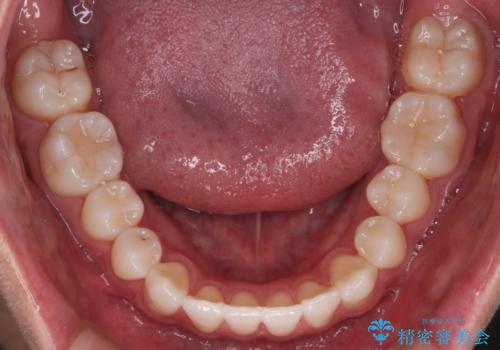

右上2番が欠損しているため、見た目と噛み合わせの両方のバランスを整えるために経過を追いながら必要な部位にゴム掛けをしました。

最終的に、見た目も噛み合わせも患者様に満足いただけました。

また矯正後、患者様の希望で

メタルインレーをセラミックインレーにやりかえさせていただき、さらに綺麗に仕上がりました。